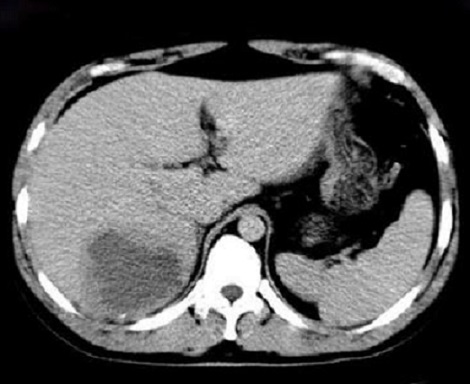

Image radiologique TDM d'une abces

amibien du foie droit avec aspect lesionnel est un masse

hypodensite a paroi epaise attenue et zone de

oedemateuse hypodense peripherique

|

Image TDM en coupe axiale :

Aspect lesionnel une

masse a central tres hypodense et de legerement

hypodensite peripherique de sa paroi situe au lobe droit du foie .

Image radiologique peut en susgeste d'une abces

amibien |